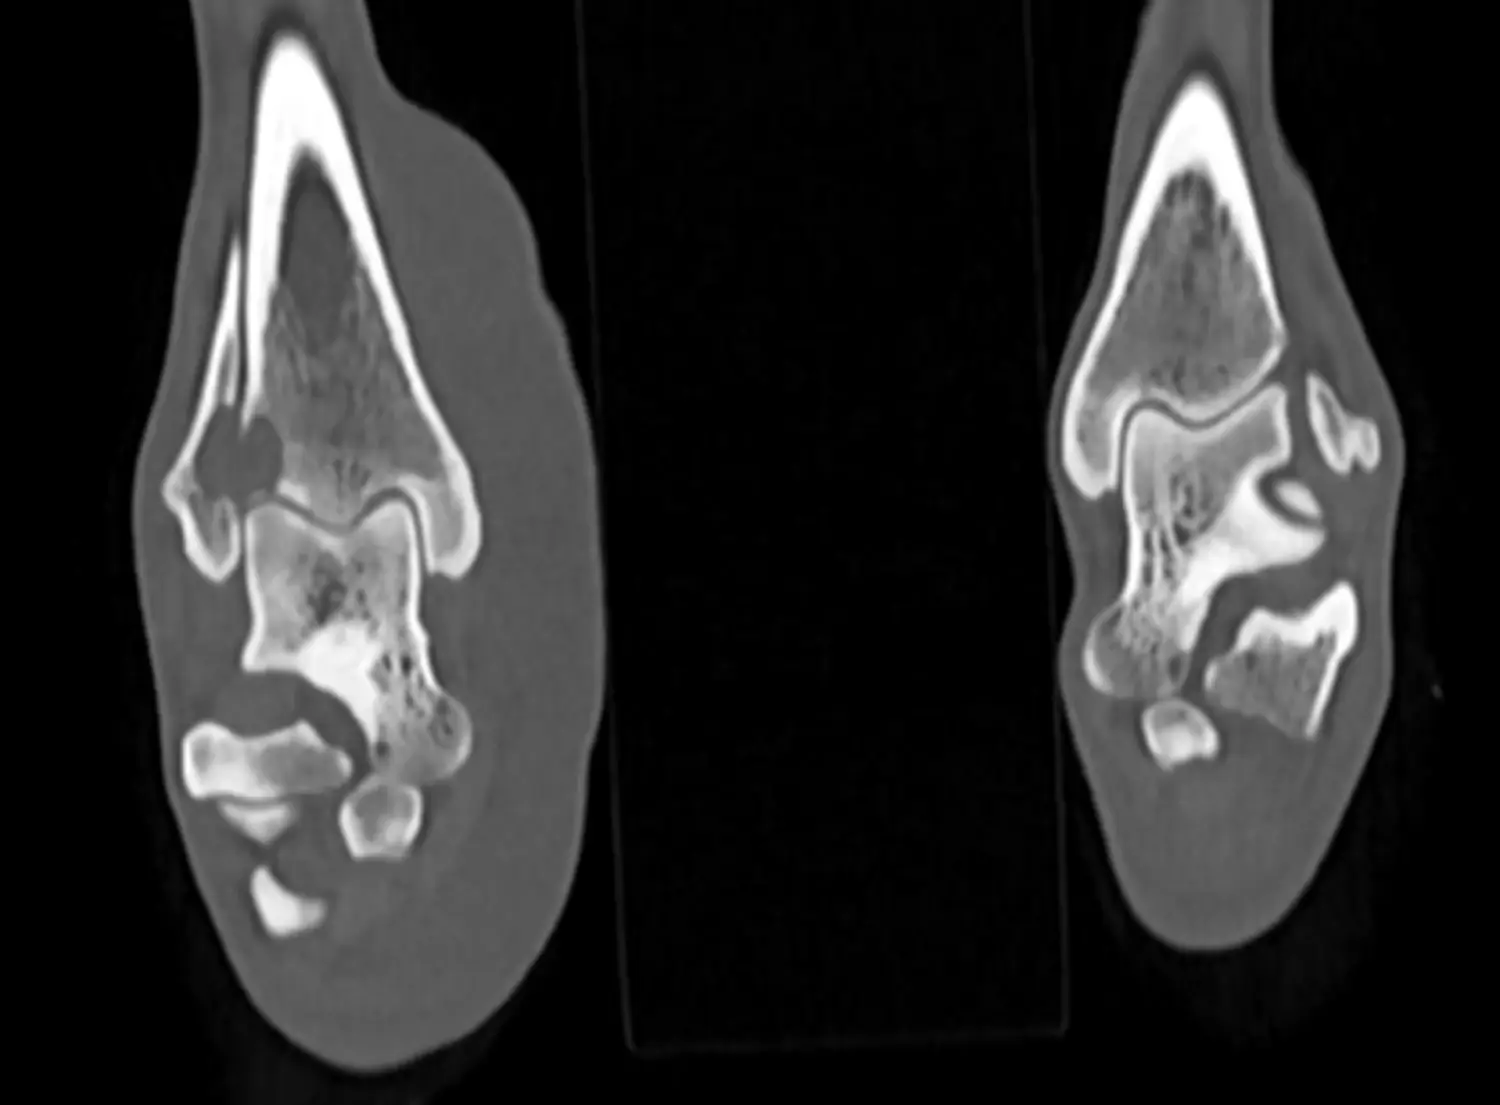

Končetiny:

ortopedická diagnostika. Plánování složitějších operací – korektivní osteotomie, vývojové anomálie končetin a kloubů – dysplazie, OCD atd. Komplexní fraktury velkých kostí a jejich řešení. Nádorové procesy v kostech.